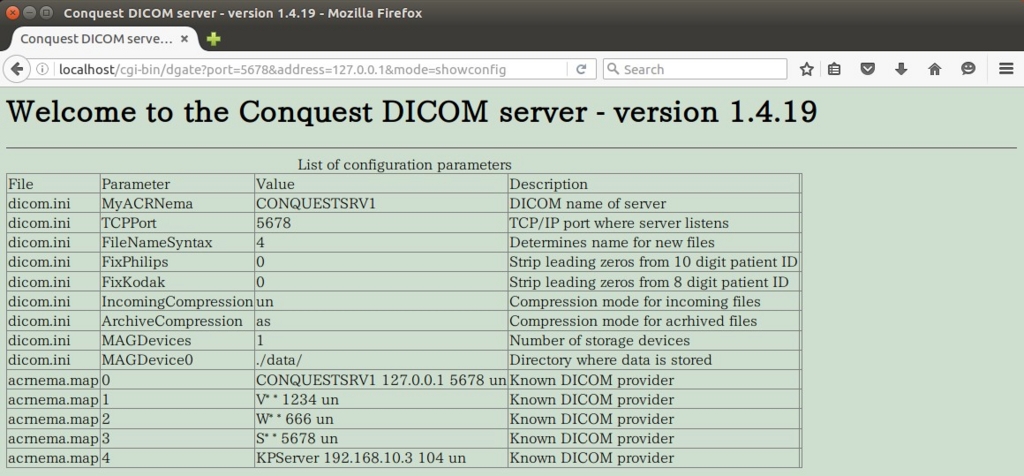

これでサーバーは構築されています。ブラウザのアドレスバーに' http://localhost/cgi-bin/dgate?mode=top 'と入力すると。

次にクライアントのKPACSに接続するための設定です。

ブラウザで確認。

設定が反映されます。